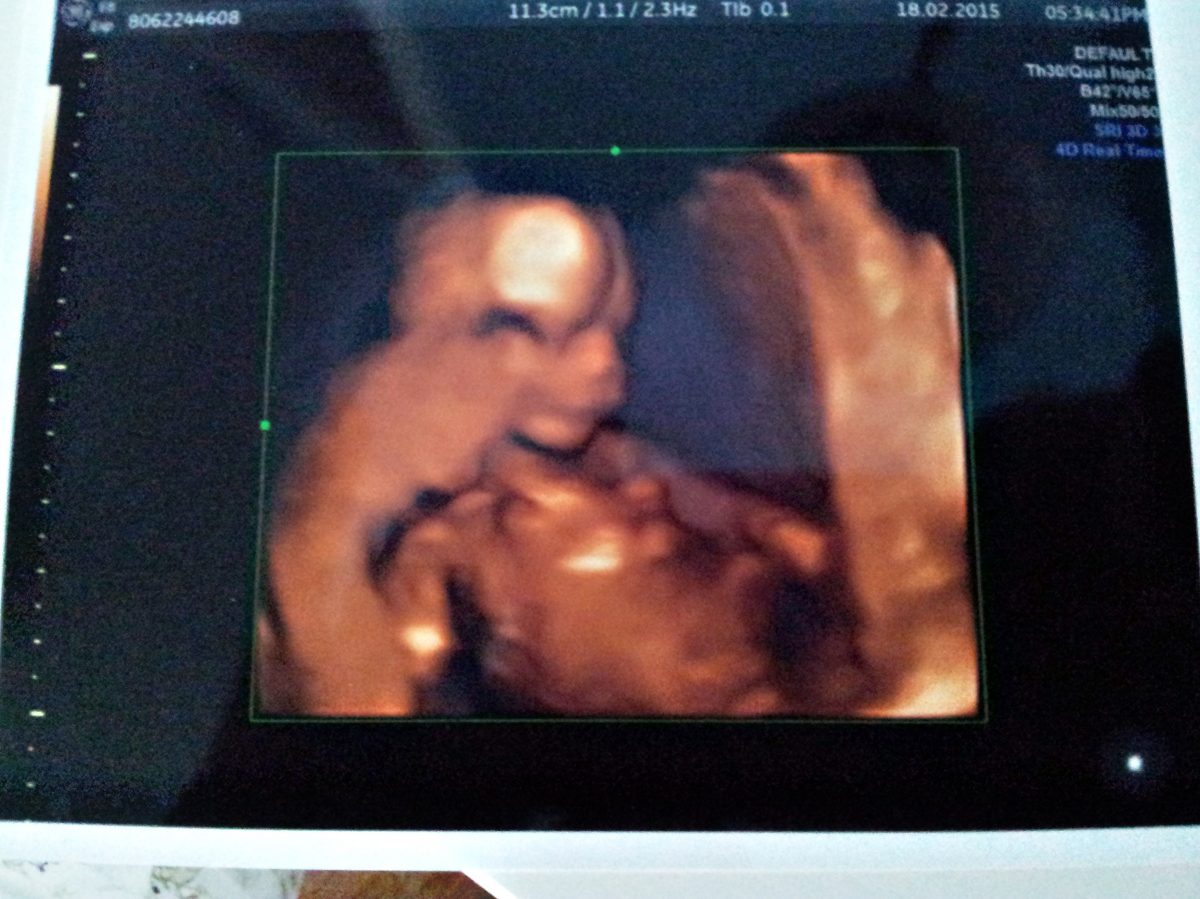

Fotografie (15. týden nového života)

Fotografie (15. týden nového života). Zdroj: archiv redakce